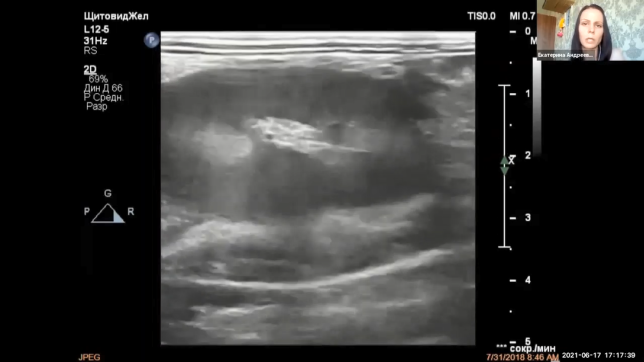

II. Детальный разбор частых случаев патологий почек кошек

Десять невероятно интересных клинических случая от Надежды Крутицкой, Наталии Прокофьевой, Лемары Войтовой и Екатерины Андреевой